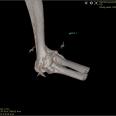

Die Orthopädie beschäftigt sich mit der Entstehung, Verhütung und Behandlung von angeborenen oder erworbenen Problemen des Bewegungsapparates. Die meist daraus resultierenden Lahmheiten werden bei uns umfassend abgeklärt. Hierbei kommen neben einer ausführlichen klinischen Lahmheitsuntersuchung auch weiterführende diagnostische Verfahren, wie Röntgen Computertomografie und Ultraschall zum Einsatz.